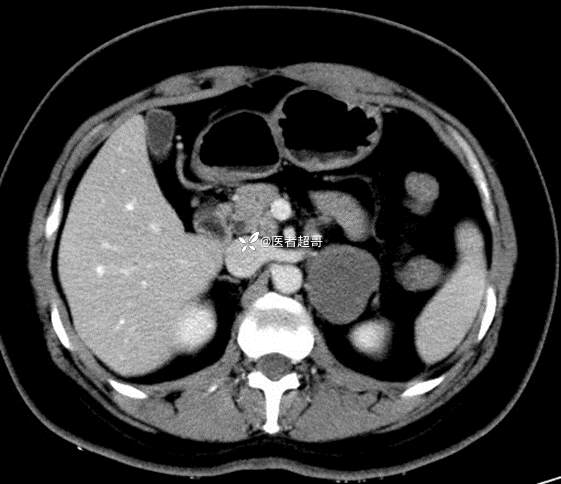

病例【影诊笔记711】女,23岁,体检发现左侧肾上腺占位,有病理,请赏析~~~

女,23岁,体检发现左侧肾上腺占位